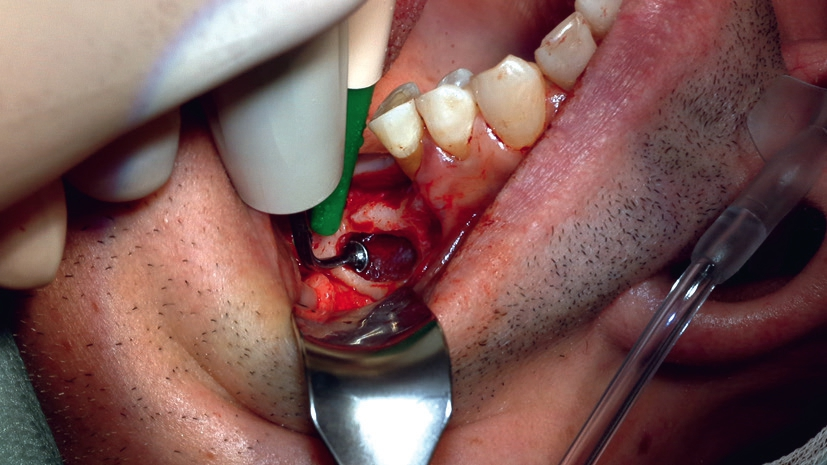

Im vorliegenden Patientenfall zeigte das DVT ein vertikales Knochenangebot von ca. 4,0 mm, sodass im Hinblick auf Größe und Durchmesser bereits im Vorfeld eine Selektierung des zu verwendenden Implantattyps getroffen werden konnte. Ebenso konnte eine häufig anzutreffende knöcherne Septierung der Kieferhöhle ausgeschlossen werden. Ebenfalls sehr wichtig ist auch die RFA, die in diesem Fall besonders große Bedeutung hatte, da bei so marginalem Knochenangebot zunächst kein hoher Implantat- Knochen-Kontakt ermittelt werden kann.

Vorhersagbarkeit der Stabilität dank RFA

Die Resonanz-Frequenz-Analyse spielt bei der Bestimmung der Implantatstabilität eine wichtige Rolle und gilt als präziser als der Periotest, der ebenfalls Anwendung findet. Sie dient damit auch zur Planung des weiteren Vorgehens.

Ist ein Wert über 70 erreicht, ist das Risiko sehr gering, dass das Implantat durch das Einbringen des Abutments aus dem Knochen gedreht wird. Nun ist eine erfolgversprechende Anbringung der Krone möglich – auch bei sehr dünnem Kieferknochen, der ansonsten schnell für instabile Verhältnisse sorgt.